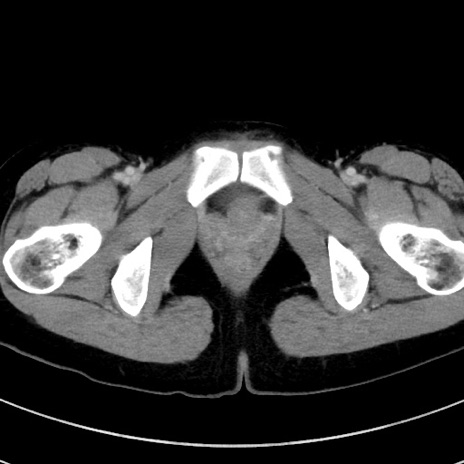

症例17(横断像)

【症例】20歳代女性

【主訴】嘔吐、下腹部痛

【現病歴】昨日夕食後に嘔吐し下腹部痛が出現。本日になっても嘔吐持続し改善しないため来院。

【身体所見】意識清明、BT 37.2℃、BP 108/67mmHg、腹部:平坦、やや硬、下腹部正中から右にかけて圧痛あり、反跳痛軽度あり、tapping pain(+)。

【データ】WBC 13600、CRP 14.94